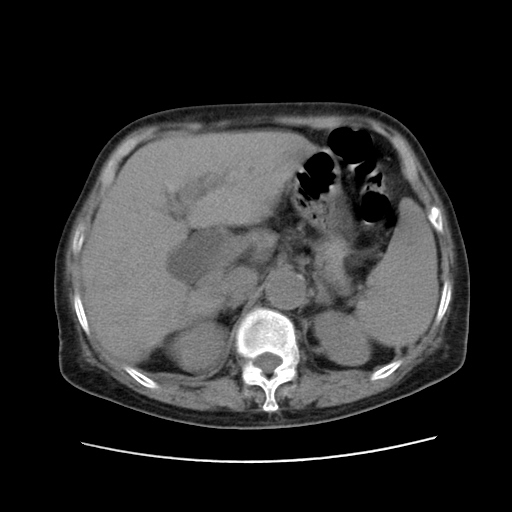

标题: CT25203:上腹部增强,看看

女,77.无不适

胆管扩张,壶腹部占位?

肝脏变异、异位胆囊,肝右叶肝内胆管结石并肝内胆管扩张。

肝内胆管扩张,胆囊炎,胆囊窝积液。 右侧胸腔少量积液。

肝右叶肝内胆管结石并肝内胆管扩张。

肝右叶肝内胆管结石并肝内胆管扩张。胆总管下段梗阻,考虑壶腹部占位。

右侧肝内胆管局限性扩张,其内密度不均匀,扩张的胆管壁增厚,考虑肝内胆管炎合并结石可能性大

肝右叶肝内胆管结石并肝内胆管扩张。胆总管下段梗阻,考虑壶腹部占位。支持